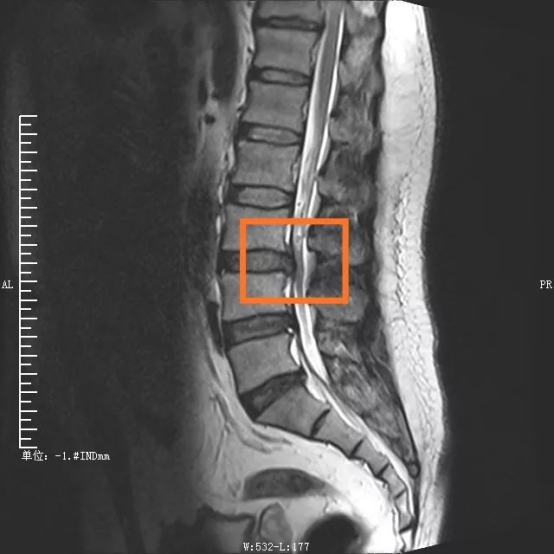

手術部位術前/術后對比圖

在外科醫生眼中,衡量一臺手術是否成功、是否屬于微創范疇,術中的出血量、組織損傷、手術時間以及術后康復時間都是重要考量因素。傳統腰椎手術從后方入路,需要切開分離肌肉組織,手術創傷大,時間長,出血量多??紤]到傳統手術對患者肌肉等組織損傷較大,且手術費用及住院時間增加,脊柱脊髓專業組決定采取更安全高效的OLIF手術。

“OLIF手術采用側方入路,手術區域在椎管前方,不破壞后方結構,不分離脊柱后方肌肉,極大地減少了組織損傷?!编嚴捉榻B,這種技術巧妙在于,充分了利用腹膜后主動脈與腰大肌前緣之間的自然間隙,到達目標椎體斜外側,結合神經外科顯微手術技術,切除病變椎間盤,實現椎間融合。若手術順利,術中患者出血僅20ml左右,患者術后2天就能下床活動,3天即可出院。